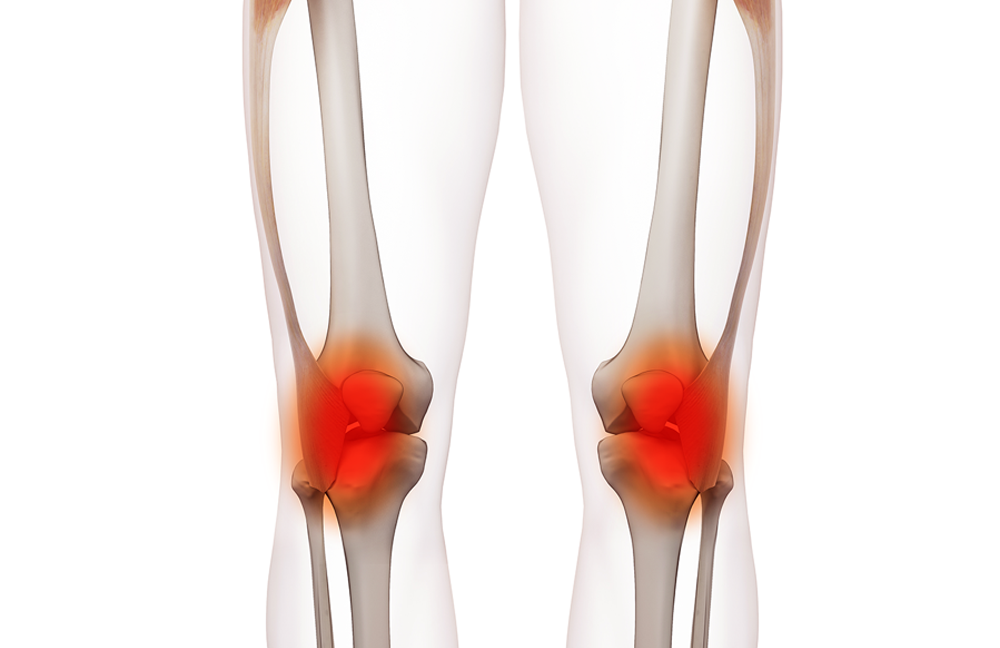

Tendonitis

Understanding Tendonitis: Causes, Symptoms, and Treatment Options Tendonitis, also known